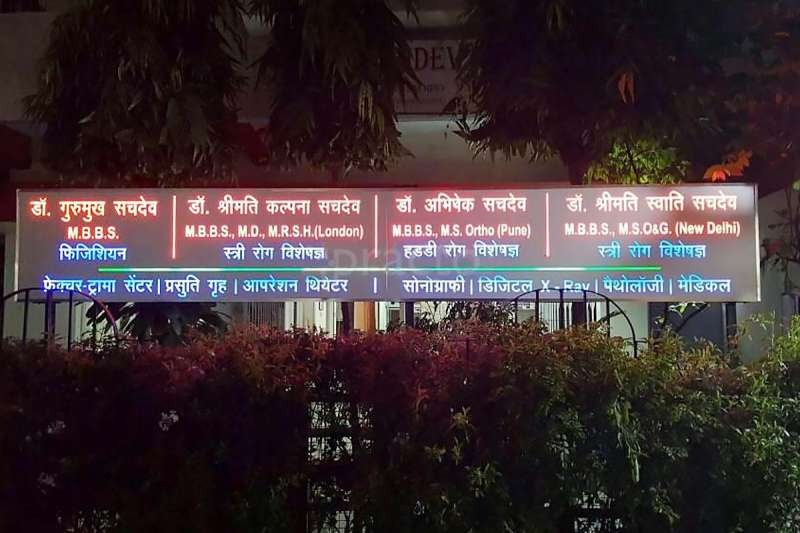

About the Doctor

Dr. Abhishek Sachdev is an experienced Orthopaedic Surgeon with over 15 years in orthopaedic healthcare. He is dedicated to providing “World Class” orthocare at reasonable cost, focusing on accurate diagnosis and evidence-based treatment.

His areas of expertise include joint pain and replacement, fracture treatment and surgery, back and neck pain, sports injuries, diabetic foot problems and high-risk wound care.

At his clinic in Sachdev Nursing Home, Samta Colony, patients receive personalised care — from clear explanation of the problem to choosing between conservative management and surgery whenever needed.